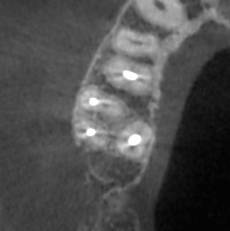

Александр В.В. Опубликовано 29 марта, 2023 Поделиться Опубликовано 29 марта, 2023 (изменено) Здравствуйте! Уже давно на шестом верхнем зубе есть гранулёма или киста размером 5-6 мм. Несколько лет назад пробовали класть кальций в каком-то виде, но, видимо, не помогло. Сейчас всё-таки решил перелечить этот канал, но эндодонтист сказал, что это только часть дела и надо делать все каналы. Кроме того, как я понял, проблема не в том канале, который запломбирован, а в том, который проходит рядом с ним и не был обнаружен и запломбирован. На этом снимке это верхний левый корень и в его правой части темное пятно - это вроде и есть тот ненайденный канал. Здесь видна гранулёма и запломбированный канал (корень слева). А здесь справа от запломбированного канала (левого корня), тот самый незапломбированный. Но у меня есть сомнения по поводу такого вывода, потому что в других каналах можно обнаружить более очевидные "темные каналы" в зависимости от среза. На этих снимках обращаю ваше внимание на правый канал. Если нужно, могу предоставить другие проекции, потому что имею диск с данными КЛКТ. Вопросы. 1. Действительно ли на снимке ненайденный канал на корне зуба с гранулёмой? 2. Возможно ли перелечивание одного канала с гранулёмой или кистой или нужно распломбировать сразу все каналы во всех корнях? 3. Если на снимке всё-таки ненайденный канал, то не кажется ли вам, что он прямой, а не изогнутый? Если прямой, его может обработать терапевт без использования микроскопа? Изменено 29 марта, 2023 пользователем Александр В.В. Ссылка на комментарий